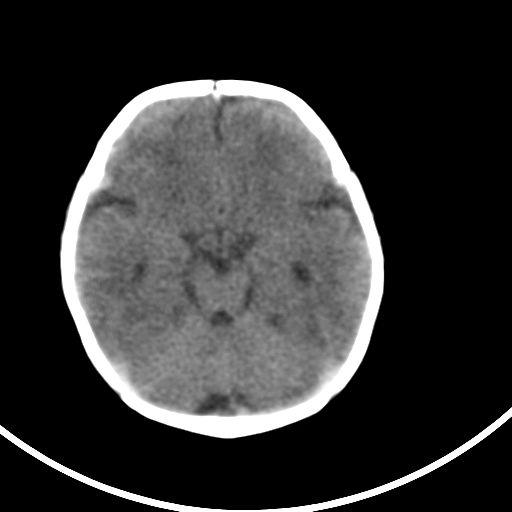

新生儿3天,超过预产期5天剖宫产,有缺氧病史,具体评分不详,现反应差,肌张力低,前囟平,原始反射存在,无苦闹等。

正常

颅底骨质影,正常颅脑表现。

正常颅脑表现。

kaolv小脑幕,后纵裂区蛛网膜下腔出血;轻度脑肿胀

未见明显异常

矢状窦旁征——支持蛛网膜下腔出血

颅脑ct平扫未见异常。

新生儿正常颅内表现

sah。